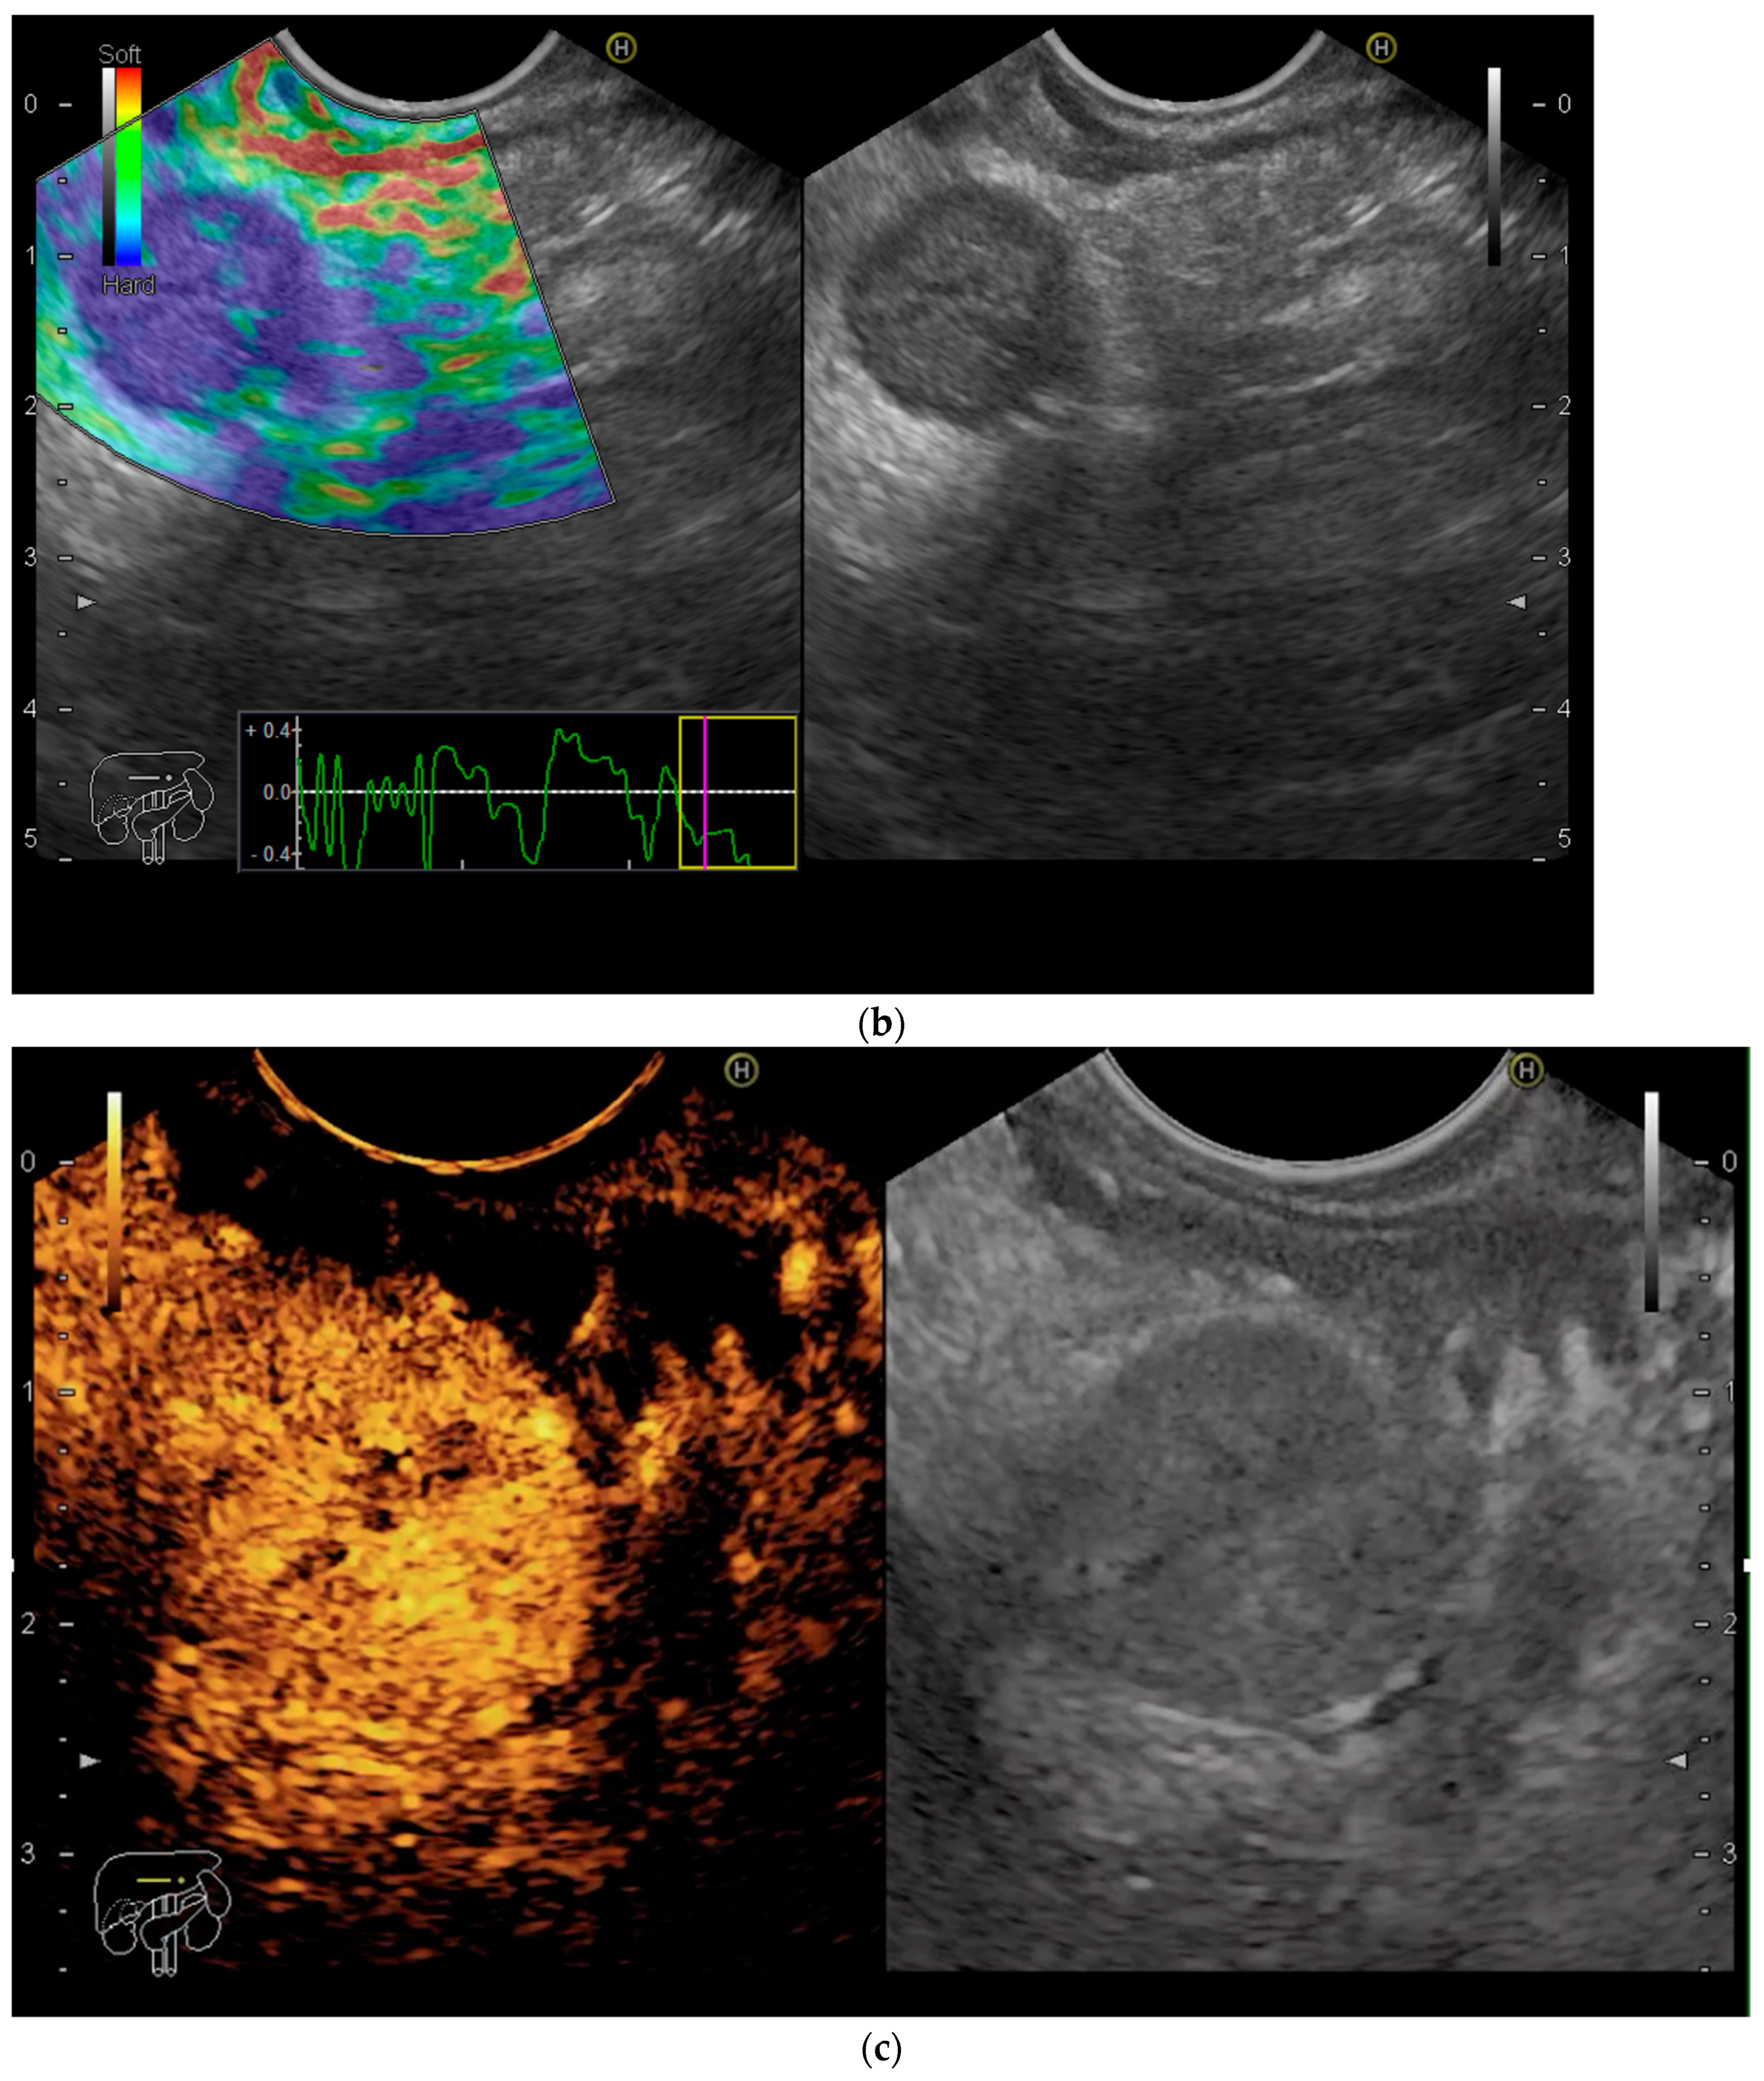

- Seicean, A.; Mosteanu, O.; Seicean, R. Maximizing the endosonography: The role of contrast harmonics, elastography and confocal endomicroscopy. World J. Gastroenterol. 2017, 23, 25–41. [Google Scholar] [CrossRef]

- Iglesias-Garcia, J.; Lindkvist, B.; Lariño-Noia, J.; Abdulkader-Nallib, I.; Dominguez-Muñoz, J.E. Differential diagnosis of solid pancreatic masses: Contrast-enhanced harmonic (CEH-EUS), quantitative-elastography (QE-EUS), or both? United Eur. Gastroenterol. J. 2017, 5, 236–246. [Google Scholar] [CrossRef]

- Ignee, A.; Jenssen, C.; Arcidiacono, P.G.; Hocke, M.; Möller, K.; Saftoiu, A.; Will, U.; Fusaroli, P.; Iglesias-Garcia, J.; Ponnudurai, R.; et al. Endoscopic ultrasound elastography of small solid pancreatic lesions: A multicenter study. Endoscopy 2018, 50, 1071–1079. [Google Scholar] [CrossRef]